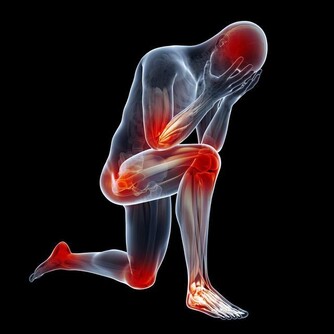

脊椎支撐著人體的上半部,對於身體健康有很大的影響,也是反映其他病痛的指標,而且背痛可不是鬧著玩的。無論生活習慣是否良好,我們都必須好好照顧自己的身體,然而要如何避免脊椎受傷或擺脫背部疼痛的風險,其實有七招日常生活中就可以執行的方式,能夠減少脊椎遭受破壞的可能性,快來看看要怎麼做吧。 廣告- ▼如果經常腰酸背痛,很有可能是你的脊椎出了問題而不自知。

▼一旦你做完這些動作,身體就會像這樣輕盈又暢快喔。